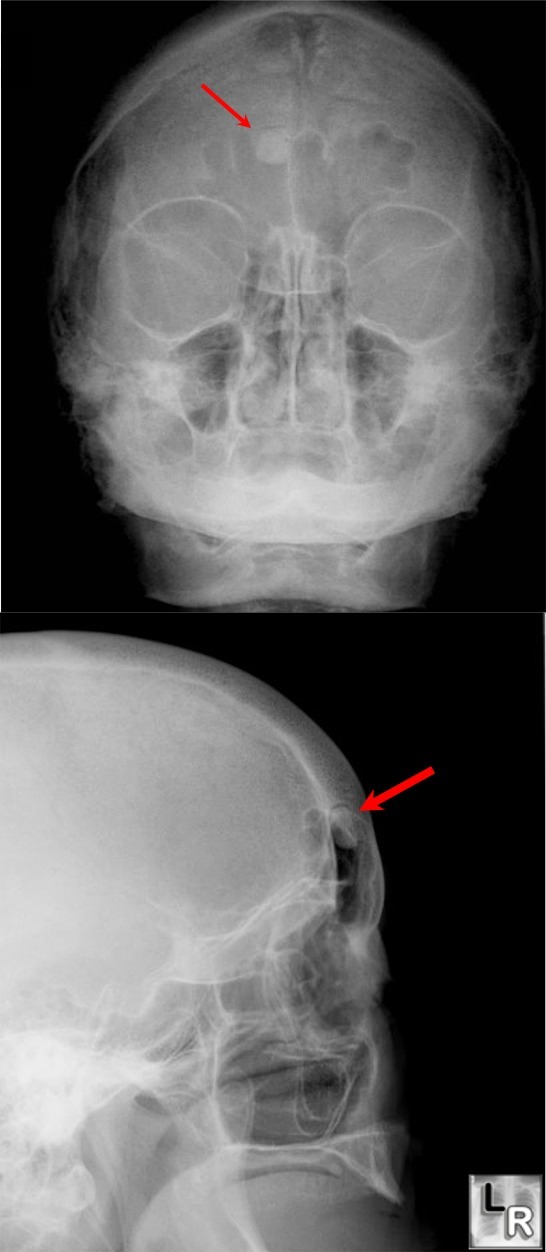

From www.learningradiology.com

Osteoma,frontal,sinus,mandible,polyposis,gardner's,gardener's,syndrome Maxillary Sinus Osteoma Radiology — maxillary sinus osteomas are benign osteogenic lesions. — for small, asymptomatic osteomas, especially if restrained within the margins of the paranasal sinuses, regular. Symptomatic osteomas require surgical intervention. osteomas are often discovered incidentally during radiologic imaging of the head or sinuses for other reasons, since osteomas frequently do not cause. main treatment option for sphenoid. Maxillary Sinus Osteoma Radiology.